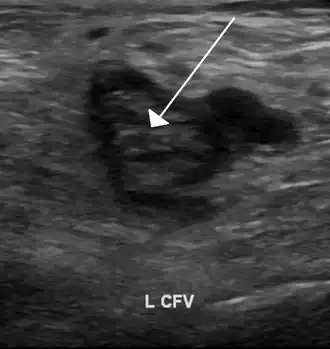

Compression ultrasonography for suspected deep vein thrombosis is the standard diagnostic method, and it is highly sensitive for detecting an initial DVT.[118] A compression ultrasound is considered positive when the vein walls of normally compressible veins do not collapse under gentle pressure.[39] Clot visualization is sometimes possible, but is not required.[119] Three compression ultrasound scanning techniques can be used, with two of the three methods requiring a second ultrasound some days later to rule out the diagnosis.[118] Whole-leg ultrasound is the option that does not require a repeat ultrasound,[118] but proximal compression ultrasound is frequently used because distal DVT is only rarely clinically significant.[117] Ultrasound methods including duplex and color flow Doppler can be used to further characterize the clot[117] and Doppler ultrasound is especially helpful in the non-compressible iliac veins.[119]

-

An ultrasound with a blood clot visible in the left common femoral vein. (The common femoral vein is distal to the external iliac vein.)